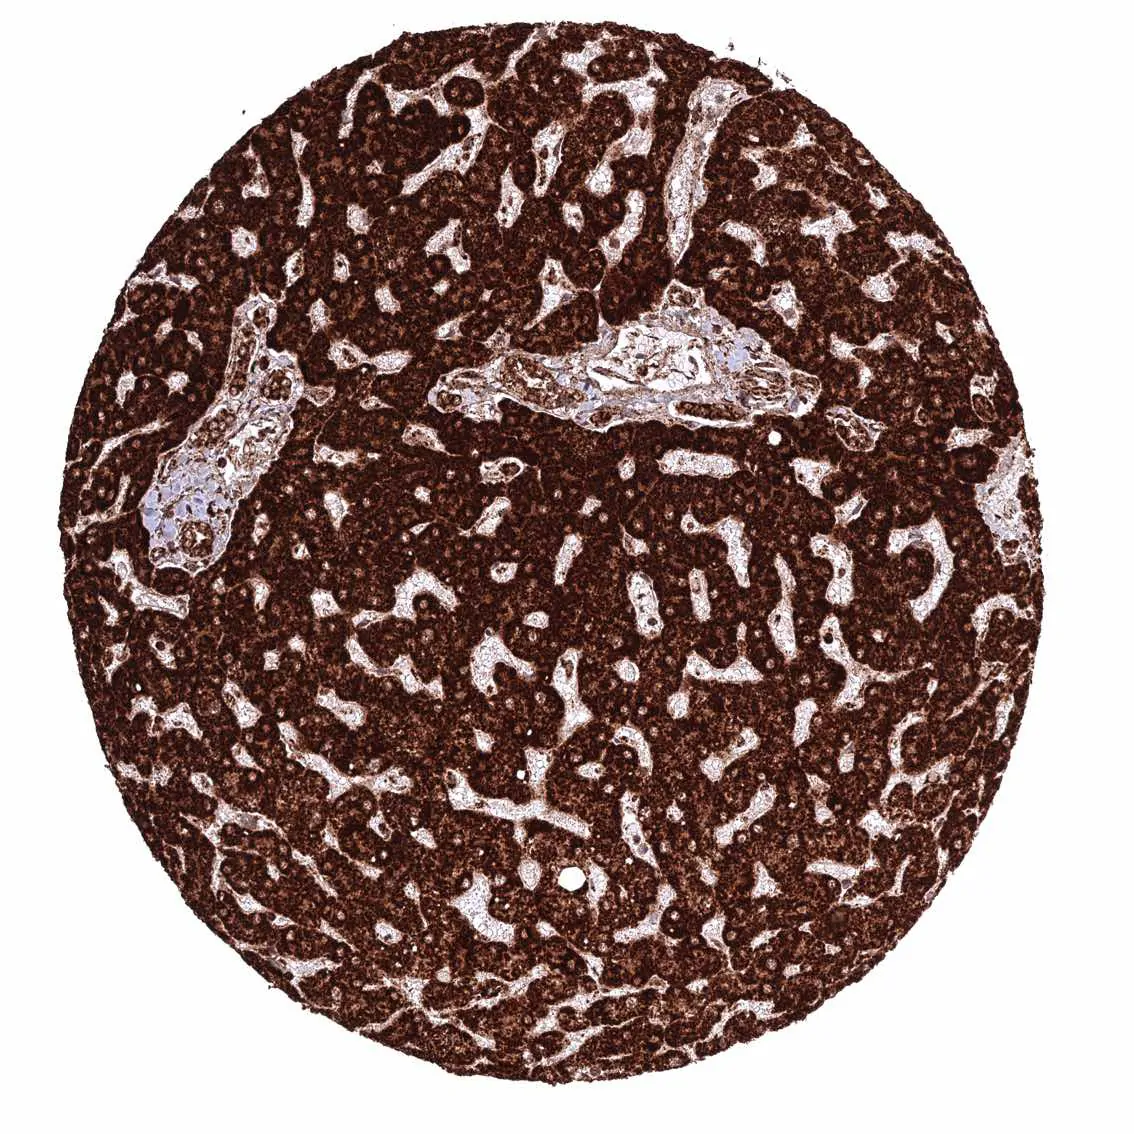

Liver – Cytoplasmic ATP5J staining is particularly intense in hepatocytes.